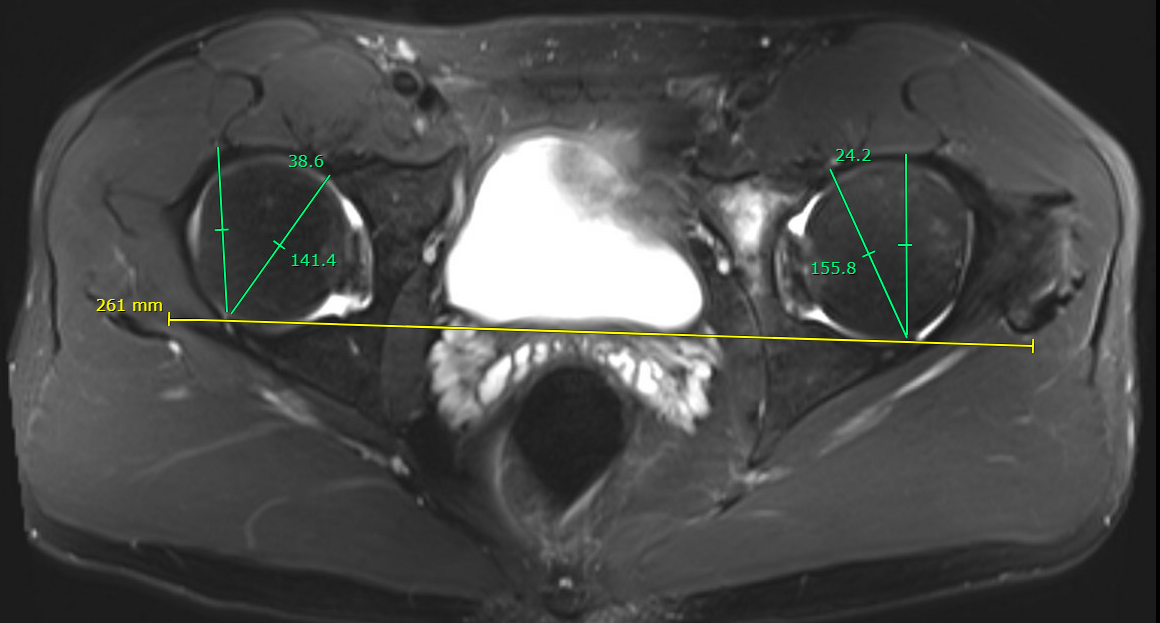

MRI alpha angle

Alpha angle

Measurement

- centered in the center of the femoral head (best fit circle)

- formed by two lines

- one line center of the femoral neck axis

- a line where the femoral head leaves a best-fit circle

- higher alpha angle with Cam lesion